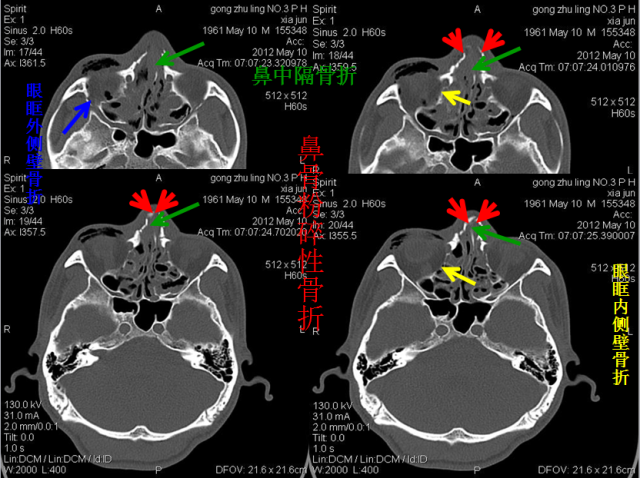

骨折篇

定义:骨折{Fracture}是指骨的完整性和连续性的折裂或粉碎。包括创伤性骨折、疲劳性骨折和病例理性骨折。 临床上以创伤性骨折*常见。